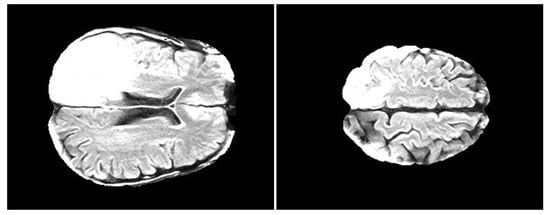

2.3. FLAIR Preprocessing

- FLAIRs were optimized by removing fat tissues and by performing skull stripping. The preprocessing steps, namely the removal of fat tissues and skull stripping, were performed by using the deep-learning algorithm described in Reference [52] (https://github.com/JanaLipkova/s3).